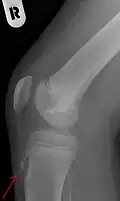

Rayos X mostrando la enfermedad de Osgood-Schlatter -

Aspecto lateral de la pierna derecha.La tuberosidad de la tibia se marca al centro derecha